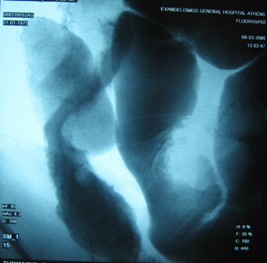

Στους ίδιους ασθενείς η εντερόκλυση μπορεί να αναδείξει ανάλογα ευρήματα με την ενδοσκοπική κάψουλα (εικόνες 36-43) ή να είναι φυσιολογική (εικόνες 44-48).

38  39

Εικόνα 38. Ο ίδιος ασθενής με τις εικόνες 10,13.          Εικόνα 39. Ο ίδιος ασθενής με τις εικόνες 33,34.

Στένωση τελικού ειλεού                                                  Εξελκώσεις τελικού ειλεού